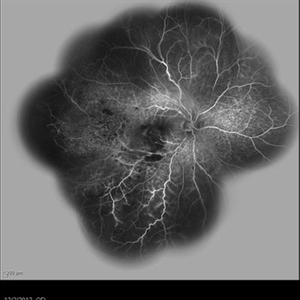

Behcet's Disease Behcet's DiseaseMar 13 2013 by Hamid Ahmadieh, MD Early phase FA of the left eye of a 23-year-old man with retinal vasculitis due to Behcet's disease . Photographer: Solmaz Shahmohammad, Negah Eye Center, Tehran Imaging device: Heidelberg Spectralis Condition/keywords: retinal vasculitis

Behcet's Disease Behcet's DiseaseMar 13 2013 by Hamid Ahmadieh, MD Mid phase FA of the left eye of a 23-year-old man with retinal vasculitis due to Behcet's disease . Photographer: Solmaz Shahmohammad , Negah Eye Center, Tehran Imaging device: Heidelberg Spectralis Condition/keywords: retinal vasculitis

Behcet's Disease Behcet's DiseaseMar 13 2013 by Hamid Ahmadieh, MD Late phase FA of the left eye of a 23-year-old man with retinal vasculitis due to Behcet's disease . Photographer: Solmaz Shahmohammad, Negah Eye Center, Tehran Imaging device: Heidelberg Spectralis Condition/keywords: retinal vasculitis

Behcet's Disease Behcet's DiseaseMar 13 2013 by Hamid Ahmadieh, MD Wide field FA of the left eye of a 23-year-old man with retinal vasculitis due to Behcet's disease . Photographer: Solmaz Shahmohammadi , Negah Eye Center, Tehran Imaging device: Heidelberg Spectralis Condition/keywords: retinal vasculitis